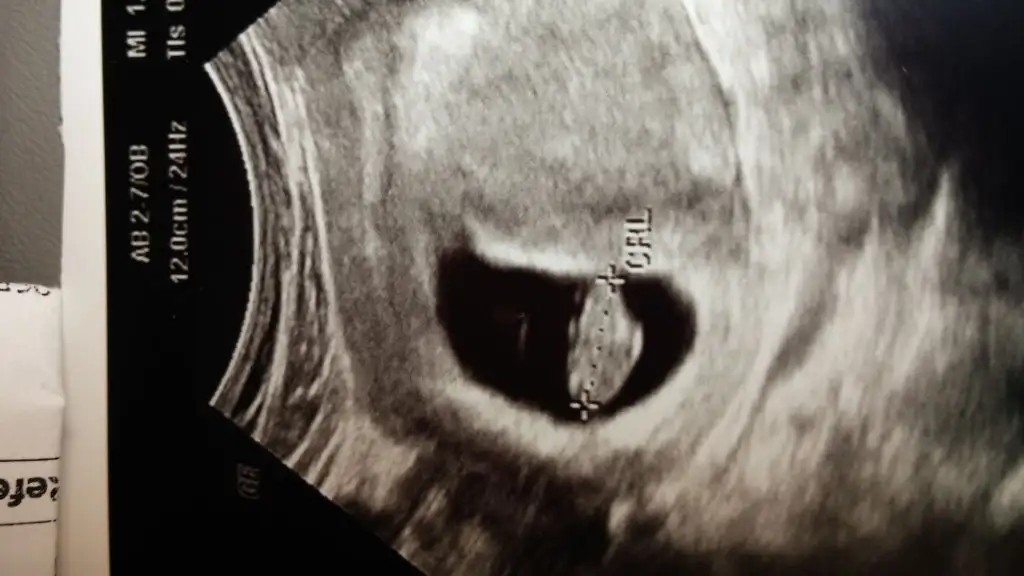

• IMG-20150728-WA0004.webp

IMG-20150728-WA0004.webp

24 KB · Görüntüleme: 207

Ustteki oglumun ultrason resmi 8 haftalik

Alttakide kardesinin 8 haftalik daha..hangisi sagda hangisi solda.